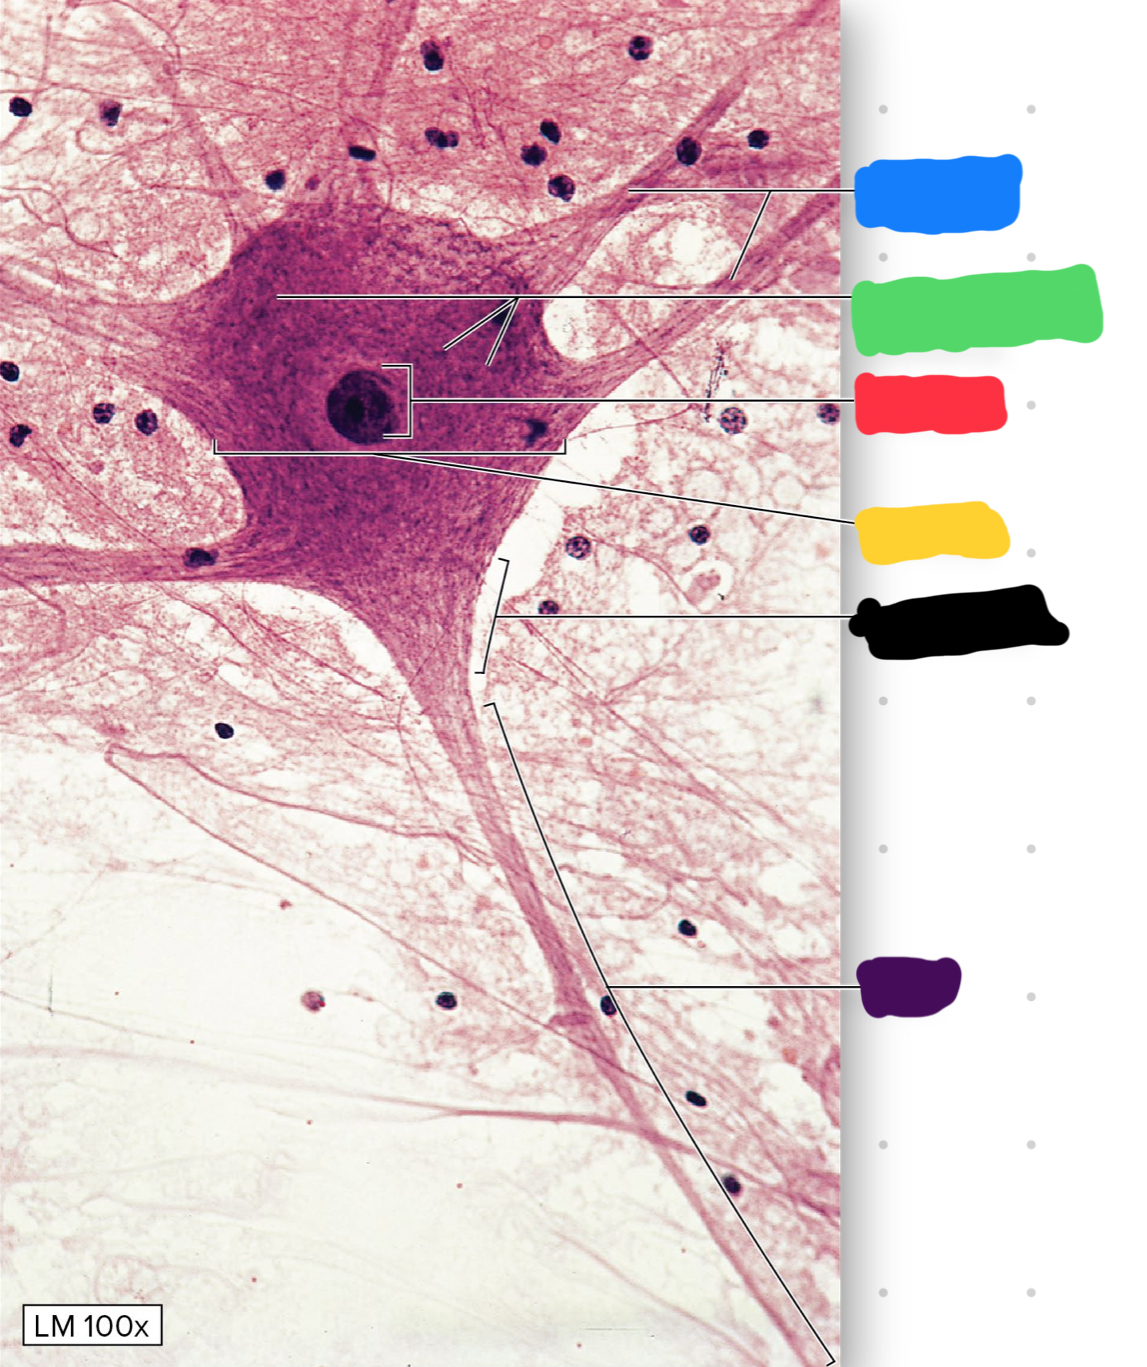

what is the blue blank pointing to on the neuron?

dendrites

what is the green blank pointing to on the neuron?

chromatophilic substance

what is the red blank pointing to on the neuron?

nucleus

what is the yellow blank pointing to on the neuron

cell body

what is the black blank pointing to on the neuron

axon hillock

what is the purple blank pointing to on the neuron

axon